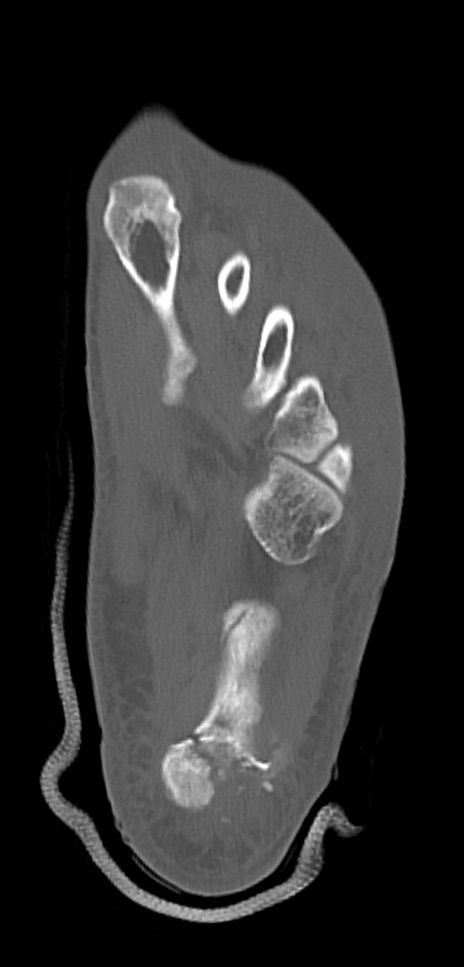

症例37 左足関節CT(横断像)

左足関節CT